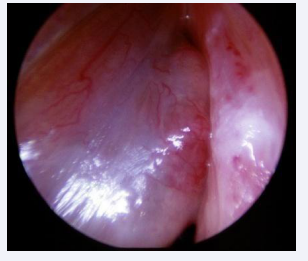

This prevalence is justified due to the surgeon’s special attention during the trans-operative period, and the following aspects were observed: the leukoplakia may be microscopic, it may be located throughout the glottis, especially at the vocal fold level, it may be associated to the initial surgical lesion, it may be contralateral to it, it may be located in the epithelium of this lesion or it may also be subglottic. Intraoperative staging with microscopy, palpation maneuvers and the use of rigid endoscopes angled at 30, 70 and 120 degrees favor the detection of leukoplastic lesions [Figures 2-5].

Leukoplakia with variation in location and quantity

Figure 5: Leukoplakia with variation in location and quantity